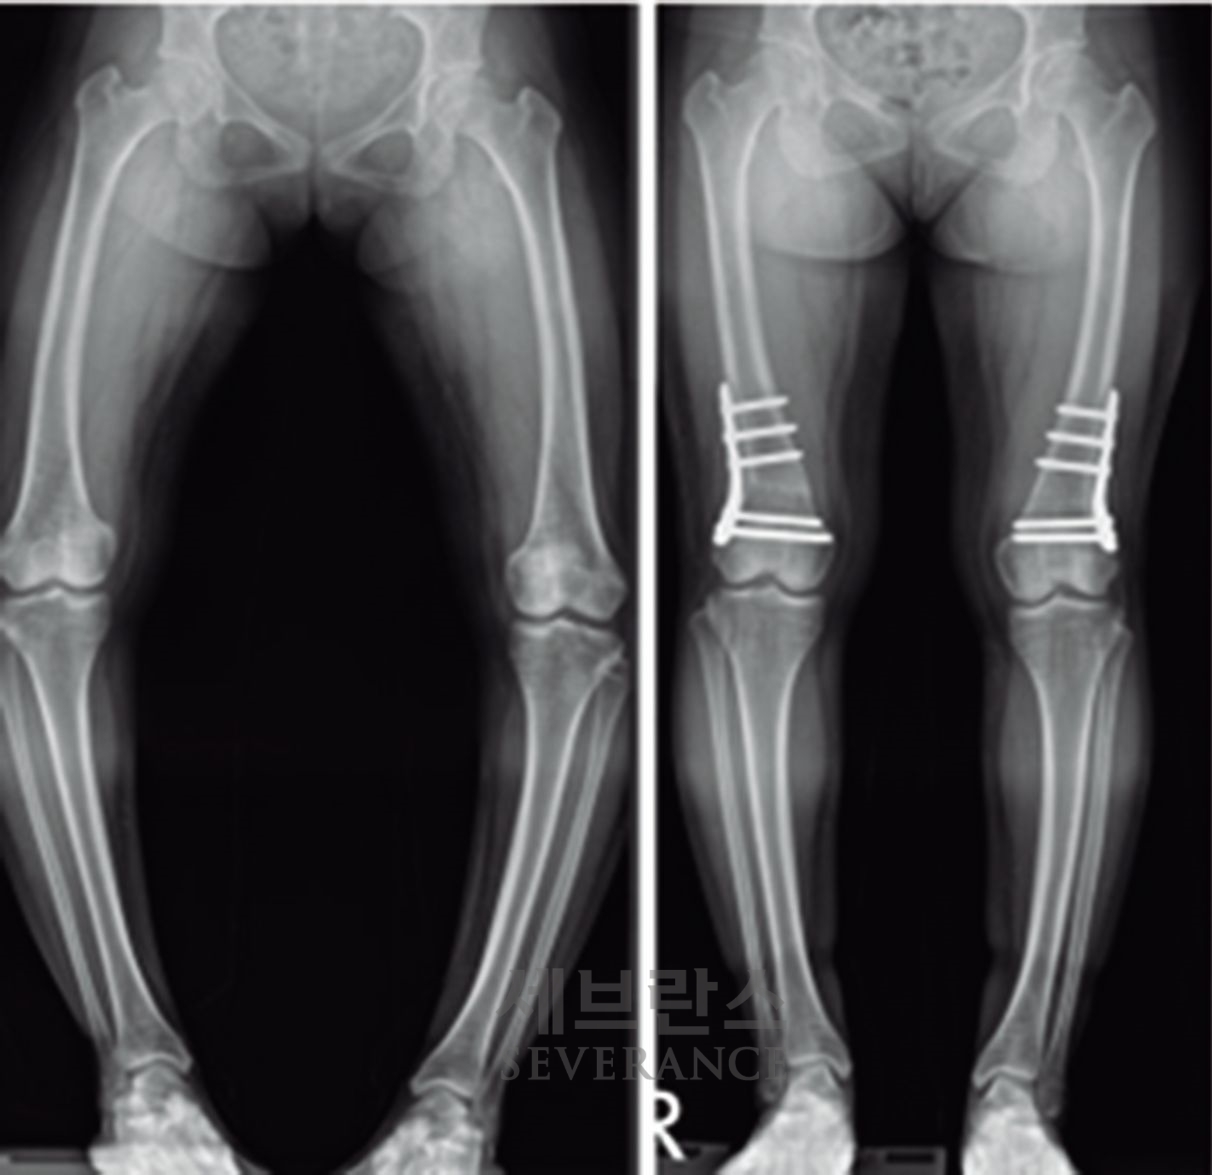

구루병으로 발생한병적 내반슬(O다리) 변형에 대해

절골 교정술을 시행한 환아

• 절골 교정술

성장이 끝난 환자나 변형이 심한 경우에는 절골 교정술이 효과적입니다. 이 수술은 뼈를 잘라 바른 위치로 되돌린 뒤 금속 장치로 고정하는 방식으로, 수술 직후 곧바로 교정 효과를 볼 수 있습니다. 그러나 절골된 뼈가 단단히 붙을 때까지 약 2-3개월이 소요되며, 그동안은 목발 보행 등 활동에 제약이 따릅니다.